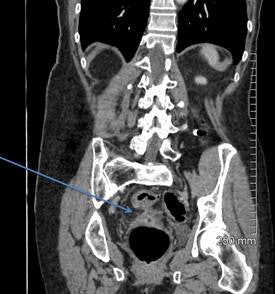

A 68-year-old woman with a fistula, categorized as C1D4E2, between the diverticular sigmoid and the vaginal vault. All images courtesy of Dr. John Hanson.